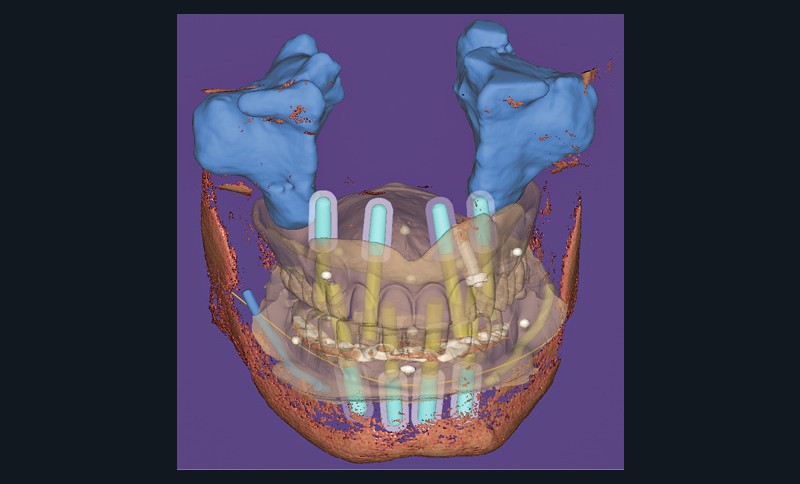

Les guides à étages sont des guides chirurgicaux statiques où chaque élément remplit un rôle lors de la pose des implants, déterminé lors de la phase de planification implantaire et de la conception de ces pièces. Une majorité de logiciels de conception par ordinateur rend aujourd’hui possible leur création, mais nécessite toutefois une expérience informatique avancée souvent réservée aux laboratoires de prothèse (fig. 1).

Un premier étage, appelé guide base, est fixé sur le maxillaire à implanter et servira de socle pour les étages supérieurs à empiler (fig. 2). Il doit être aussi rigide que stable pour supporter les contraintes pendant toute la durée de l’intervention : celles du forage implantaire comme celles des poses et déposes des étages supérieurs. Son bon positionnement est donc crucial car il déterminera celui des autres étages. Il peut également servir de repère en fin de procédure, tel un guide de scannage, pour réaliser une empreinte optique (fig. 3). Les appuis sont aussi divers qu’avec un guide statique conventionnel :

- appui dentaire : il est le plus fiable car son positionnement est permis grâce à des points fixes (fig. 4). Il reste bien sûr dépendant de la précision de l’alignement entre le STL de l’empreinte optique et le DICOM de l’examen CBCT ;